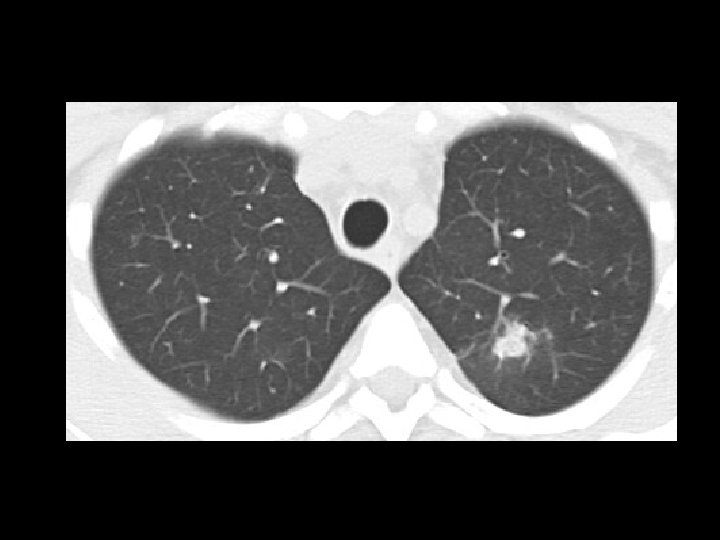

Squamous cell carcinoma • Findings: – Spiculated mass in the RUQ – necrotic center – background of emphysema • ddx: – TB – metastasis